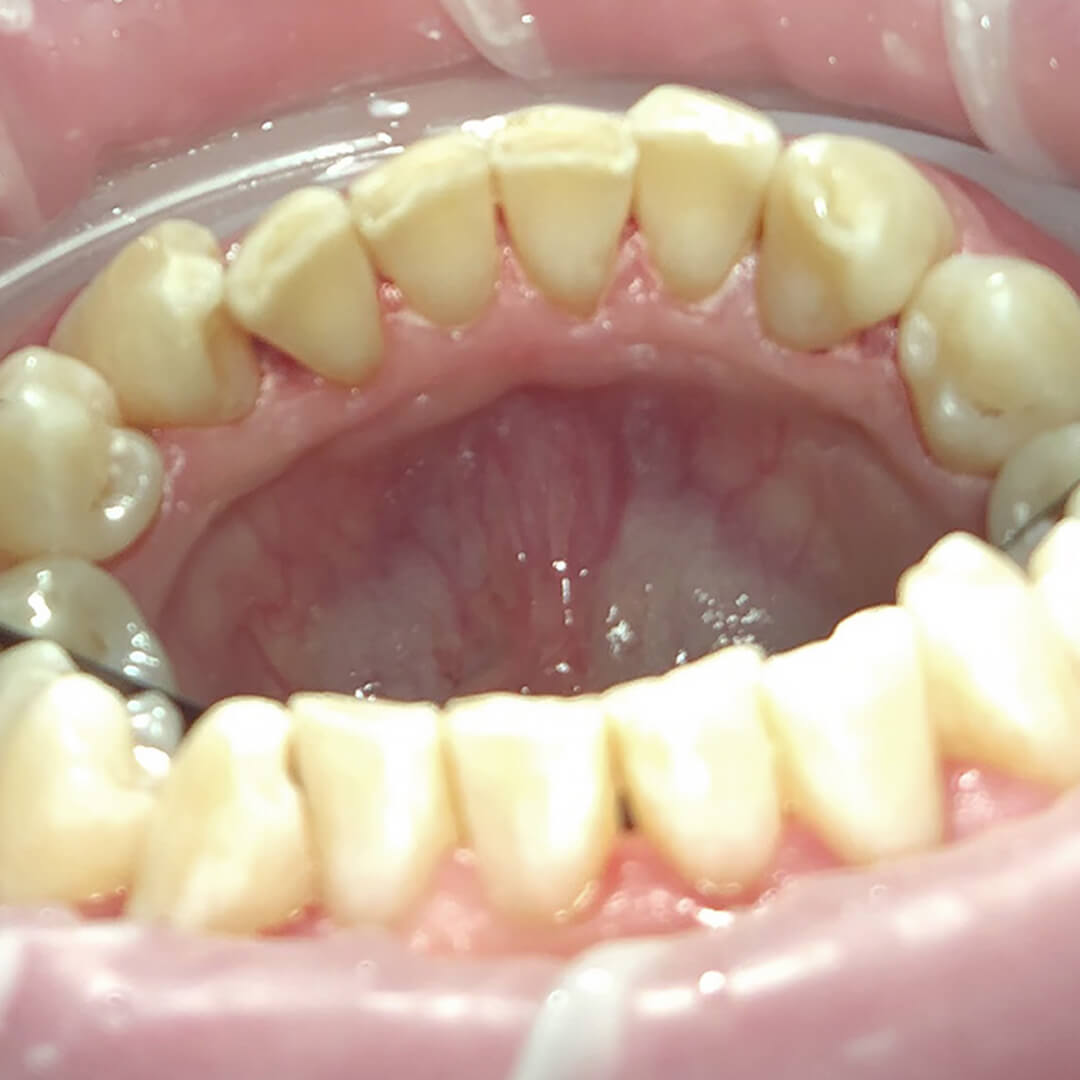

В «Стоматологию Комфорта» обратилась пациентка с жалобами на наличие зубных отложений и пигментацию. Врач-стоматолог-терапевт Луцюк Наталья Владимировна провела осмотр пациента и диагностировала хронический катаральный генерализованный гингивит. Было принято решение о проведении профессиональной гигиены с целью снятия минеральных отложений ультразвуком, а также удаления пигментированного налёта пескоструйным аппаратом и последующей полировкой пастой SuperPolish.

В ходе лечения проведены следующие работы:

- снятие минерализованных зубных отложений ультразвуком;

- удаление пигментированного налёта пескоструйным аппаратом;

- полировка зубов резиновой насадкой;

- финальная шлифовка пастой SuperPolish.